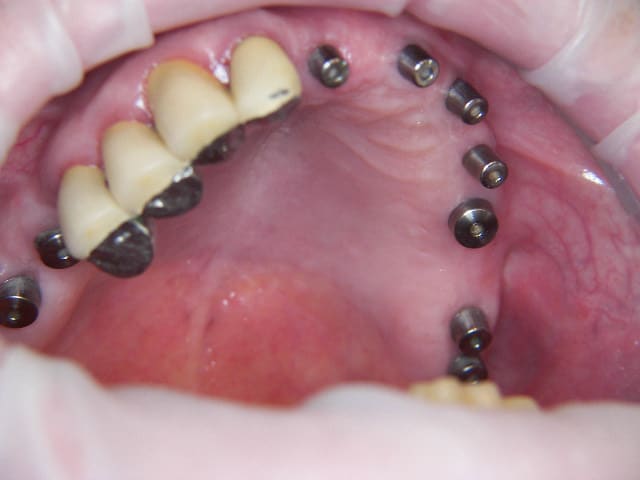

et maintenant

Img 1187 scxhsv - Eugenol

Img 1188 r4hkjo - Eugenol

Img 1189 fazbfe - Eugenol